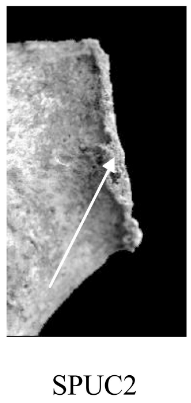

Bord postérieur (SPUC)

Aspect de la lèvre du bord postérieur de la surface articulaire.